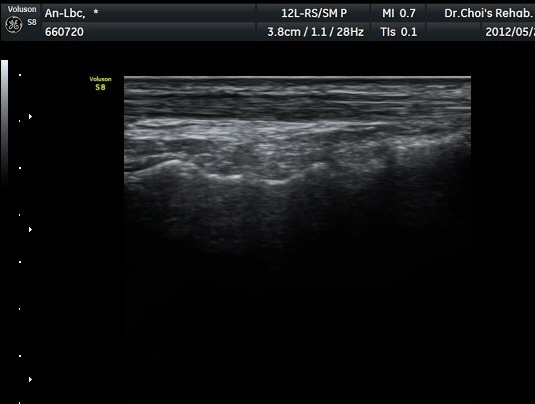

°Ç ÁÖÀ§ ¼ö¾× Àú·ù°¡ °üÂûµÈ´Ù(»çÁø 1, 2). °ÇÀÇ ºñÈÄ¿Í ¼ö¾×Àú·ù´Â °ÇÃø(»çÁø 4)°ú ºñ±³Çϸé

ºÎÁ¾°ú ¼ö¾×Àú·ù´Â °ÇÃø°ú ºñ±³ÇÏ¸é ¶Ñ·ÈÇÏ´Ù(»çÁø 5).¤·